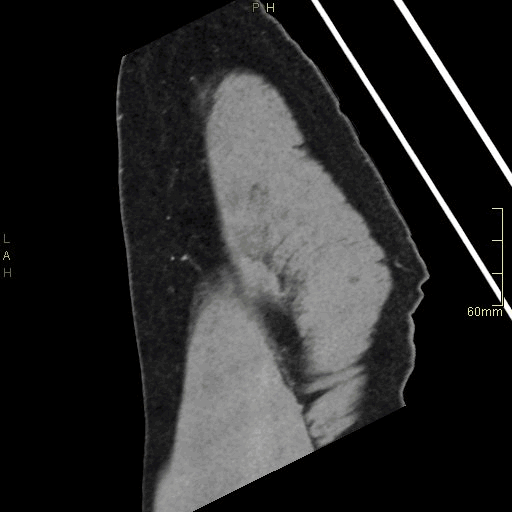

CT Hip Contrast- Soft tissue window (sagittal)

CT Hip Contrast- Bone window (sagittal)

CT Hip Non Contrast- Bone window (sagittal)